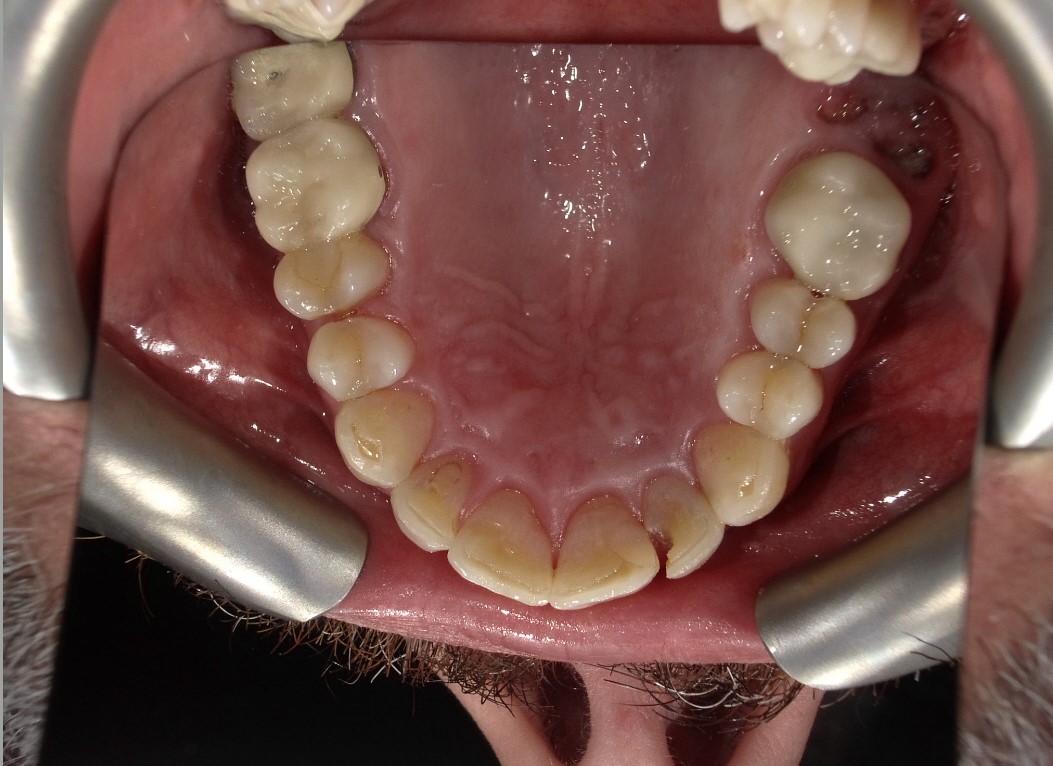

Extra-oral photography. Extra-oral photography is essential for giving patients a full picture of their smile and oral health status. This has been a challenge for most dentists over the past two decades because many cameras that have the capability of taking high-quality, fully focused images of the dental arch have been difficult to use and program and awkward to sterilize. Other dentists have limited their use of such cameras to the occasional cosmetic case. However, extra-oral photography should be provided for every patient. The use of such photography and the type of photographs taken can vary from office to office, depending on the patient flow and the availability and training of personnel at that particular office. Regardless of these variations, however, all dental practices should take the following four extra-oral photos: the close-up smile, the retracted smile, the upper arch, and the lower arch (Figure 1 through Figure 4).

Fig 1. Extra-oral photography. All dental practices should provide the patient with the following four extra-oral photographs: the close-up smile (Fig 1), the retracted smile (Fig 2), the upper arch (Fig 3), and the lower arch (Fig 4).

Fig 3. Extra-oral photography. All dental practices should provide the patient with the following four extra-oral photographs: the close-up smile (Fig 1), the retracted smile (Fig 2), the upper arch (Fig 3), and the lower arch (Fig 4).

Figure 3

Fig 4. Extra-oral photography. All dental practices should provide the patient with the following four extra-oral photographs: the close-up smile (Fig 1), the retracted smile (Fig 2), the upper arch (Fig 3), and the lower arch (Fig 4).

Figure 4